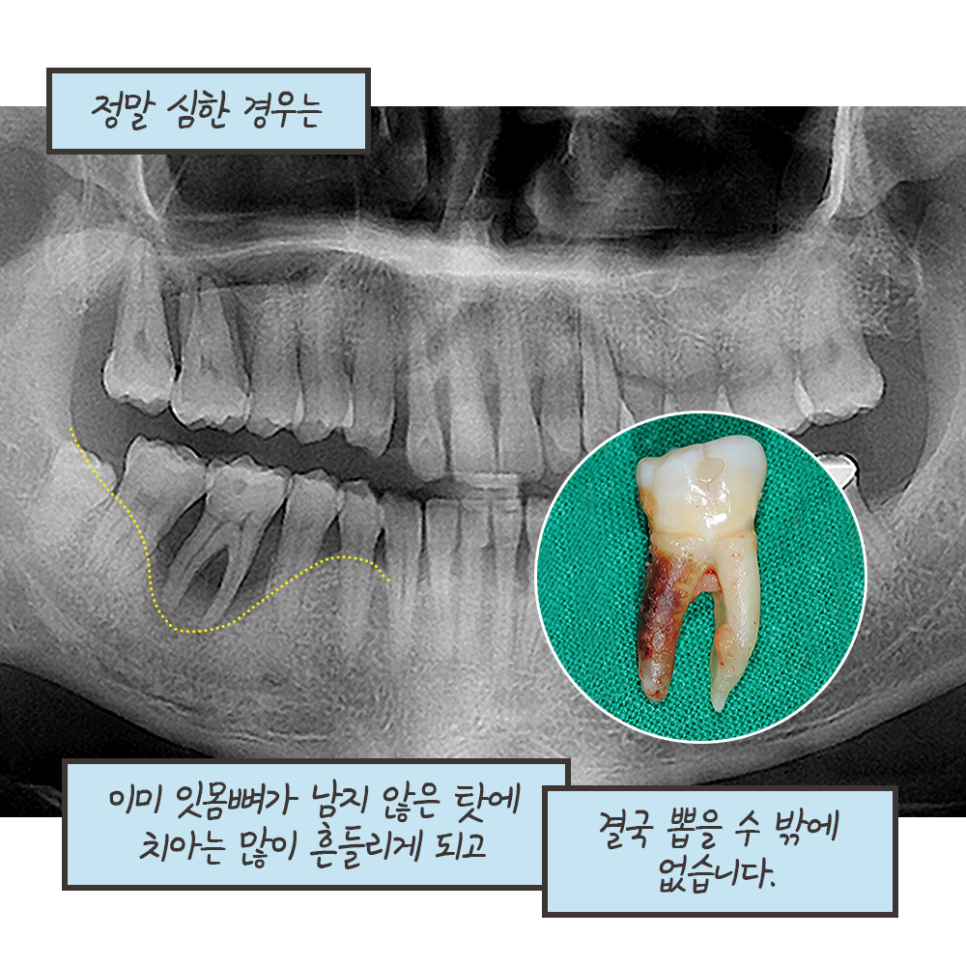

치석이 많고 염증이 심할수록

시린 증상이 더 느껴질 수 있어요.

스케일링 후 개운함만 남을 수 있도록

평소에 구강관리를 잘 해주셔야합니다~